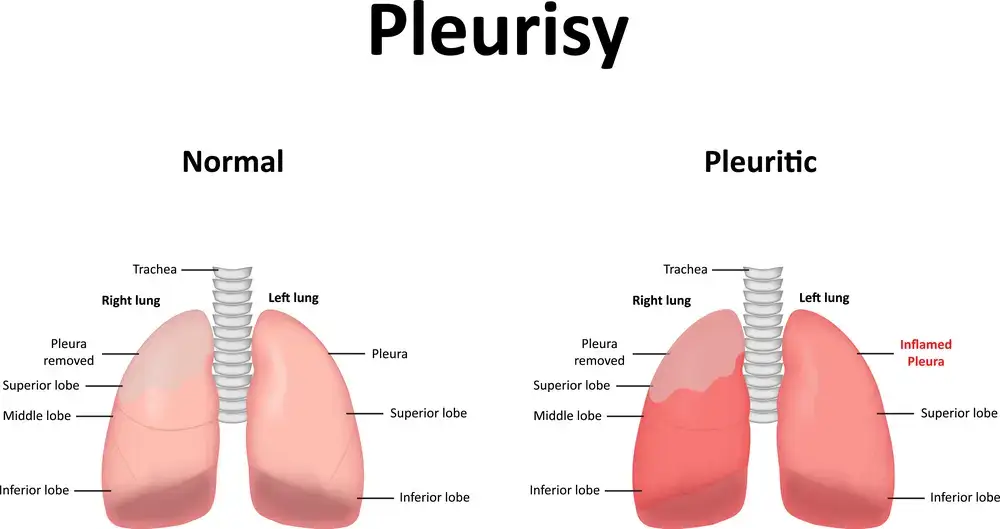

- Pleurisy • Georgetown • osteopathy • Natural Health Clinic of Halton (April 3, 2022)